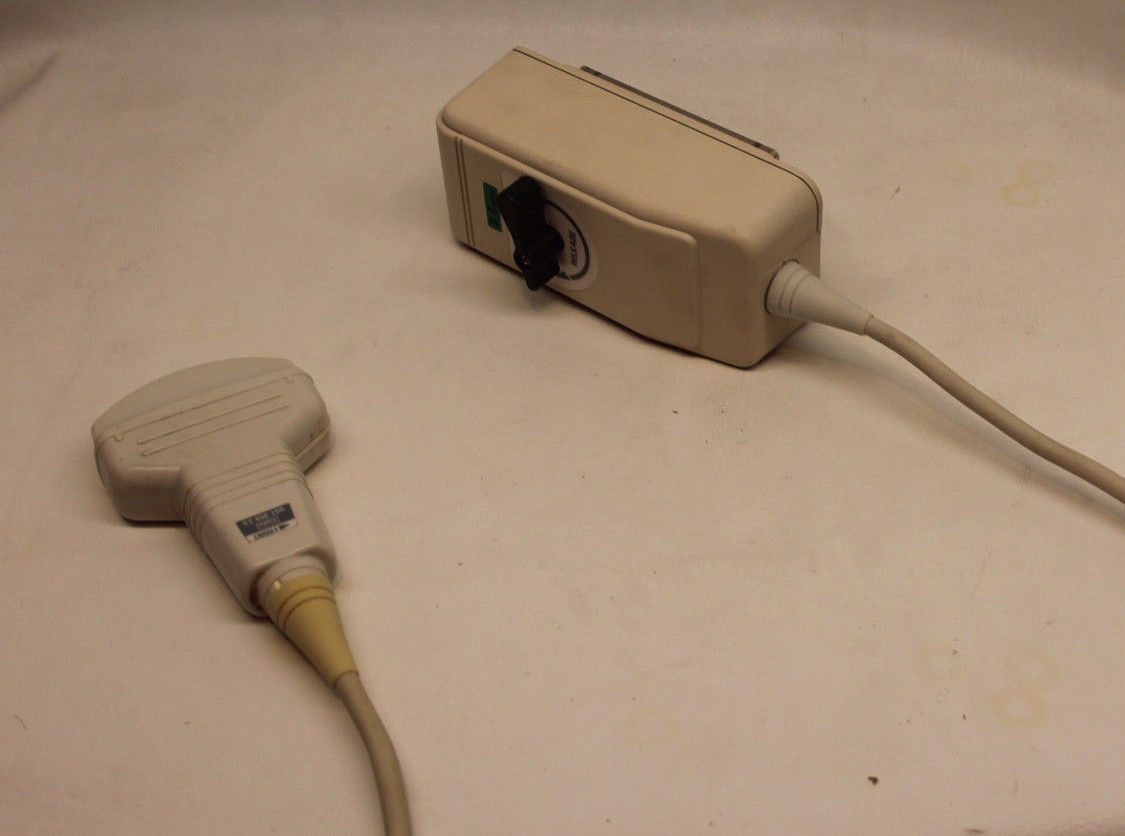

Aloka Ultrasound Probe Model: UST-959-3.5

Sale price$ 2,159.86

Aloka Ultrasound Probe Model UST-SSD830P2-5

Sale price$ 1,917.14